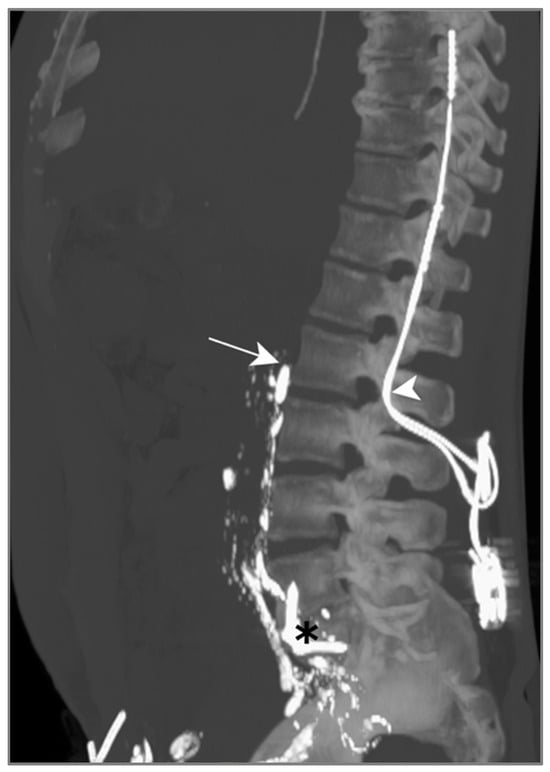

LL was attempted to visualize and potentially seal the leak, but the contrast agent did not show any progression above L2 on successive CT scans (Figure 6). We suspect this was due to a previous orthopedic intervention on the spine, inducing post-operative lymphatic tissue remodeling.

Figure 6.

Patient B. The maximal-intensity projection of the CT scan reconstructed in the sagittal plane. The progression of Lipiodol in the prevertebral lymphatic chains is demonstrated up to the level of the 2nd lumbar vertebra (white arrow). The location of a spinal neurostimulator (white arrowhead) and anterior lumbar arthrodesis material (black asterisk), both anteriorly placed, are highlighted.

Due to an electrolyte imbalance and difficult venous access, TPN was only initiated after LL. This CM however enabled a slow drain output reduction 6 days after nutrition had been begun; no other bailout procedures were necessary.

In this case, lymphangiography was unsuccessful in treating this post-operative chylothorax, due to lymphatic duct disruption post orthopedic surgery.